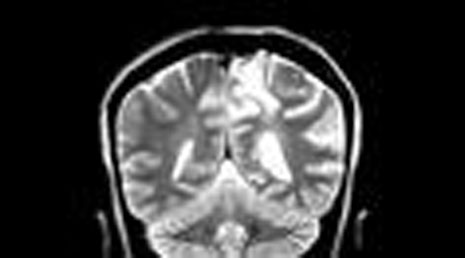

5. Aqueductal stenosis.